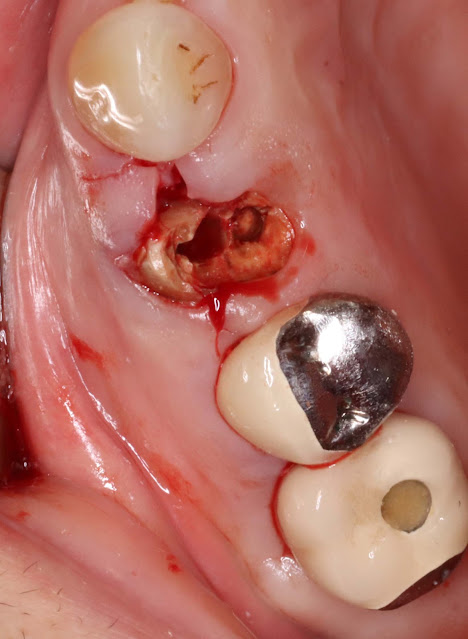

The patient is a 70-year-old woman with a fractured tooth at tooth number 24.

It has been decided to proceed with immediate implant placement.

In cases where the tooth has undergone root canal treatment, there may be some discomfort during extraction.

The tooth was eventually extracted using a drill to perform direct drilling slightly on the palatal side of the tooth during the extraction procedure.